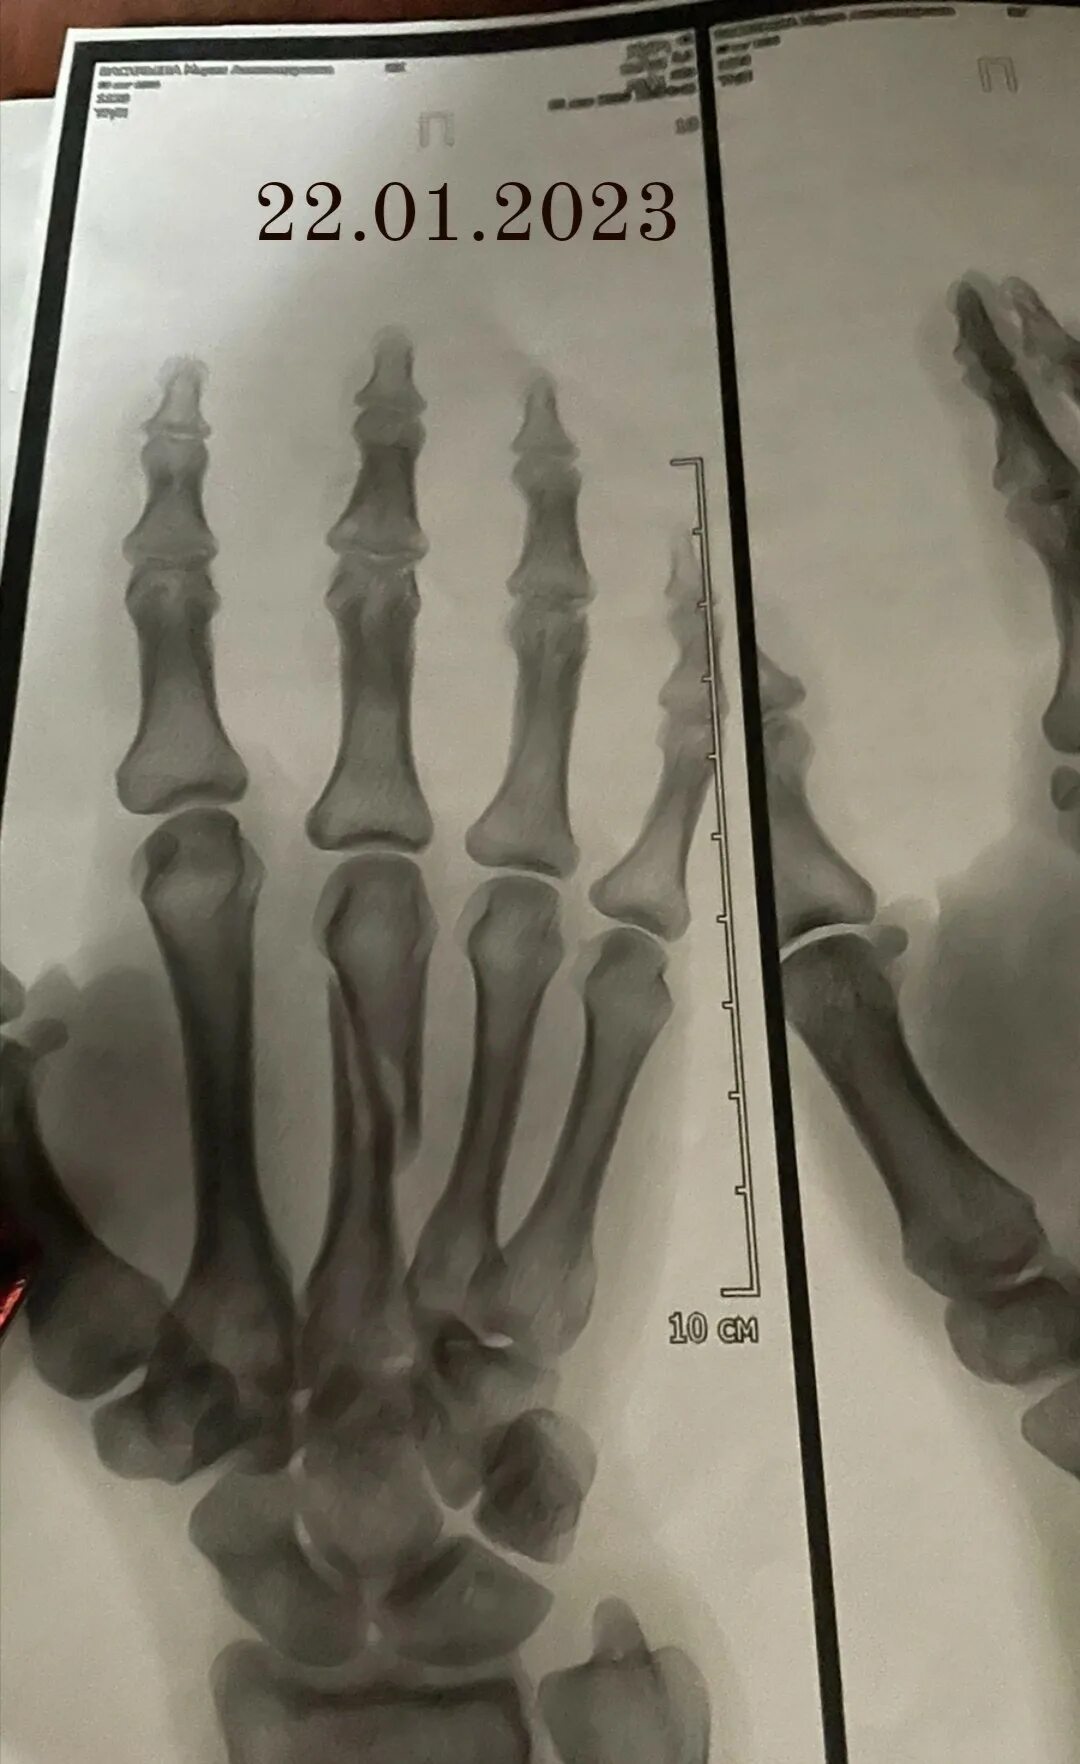

Перелом 3 пястной кости